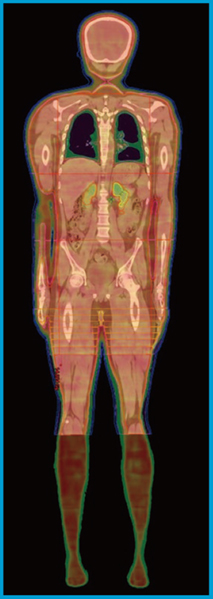

プランは下肢領域を作成後,下肢領域のプランをbase dose planとして頭部~体幹部領域のプランを作成した。下肢領域は20cmごとにisocenter(IC)を4か所設定し,各ICに2アークの照射野を作成した。接合部は2Gyから0Gyまで分割束間で線量低減を段階的に設定した。頭部~体幹部領域はICを5か所設定し,各ICの照射野数は頭部2門,上部胸部6門,下部胸部・腹部4門,骨盤部2門,接合部2門とし,最適化を行った(図2)。表1に,線量の目標値を示す。肺の平均線量率はトモセラピーによる報告の33.3cGy/minを参考に,肺野にかかる照射野を上部胸部6門と下部胸部・腹部のうち2門の計8門とした1)。Halcyonの照射時間は最短30秒/周なので,8門を肺に照射する時間は240秒となる。肺平均線量を8Gy/6回まで落とせれば,平均肺線量率は33.3cGy/min程度となる計算である。治療計画時間は輪郭描出に5時間,最適化 9回,1回の最適化計算4〜5時間で,合計40〜50時間かかった。

図2 症例1の線量分布図 |